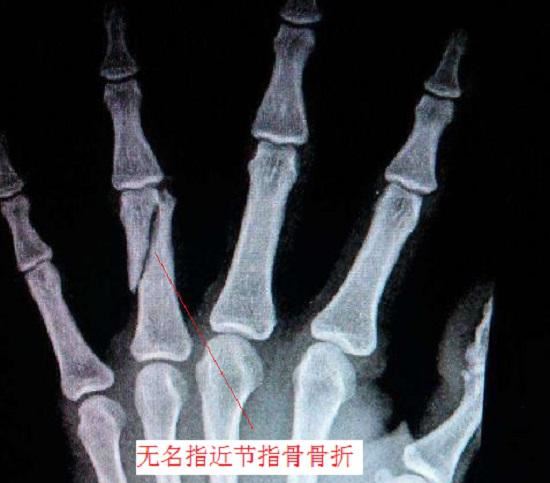

如下图所示,各掌骨上与腕部关节相连,下至手指底部、与各指近节指骨构成指掌关节;各指骨上与掌骨构成指掌关节,向下一直延伸到手的末端,共分为2-3节(拇指2节,其余指3节),各节指骨之间由指间关节相连,共同构建完整的手指。指骨骨折和掌骨骨折是上肢骨折中最常见的两个类型,二者大约占到所有上肢骨折的40%。根据骨折位置、严重程度、骨折时受力方式等方面的不同,指骨骨折和掌骨骨折还可细分为不同的类型。

掌骨骨折和指骨骨折的类型

可将掌骨骨折分为掌骨头骨折、掌骨颈骨折、掌骨干骨折、��,掌骨基底骨折。掌骨头骨折多为关节内骨折;拇指掌骨基底骨折既有关节内骨折也有关节外骨折;掌骨干和掌򏡻,。骨颈的骨折还会表现为横行骨折、斜行骨折、粉碎骨折等类型。指骨骨折也有关节内骨折和关节外骨折之分,末节指骨的关节内骨折常伴有肌腱撕脱。指骨干的骨折也有横行、斜行、螺旋形、短斜形等不同形式。不同位置、不同类型的骨折,其稳定性及治疗方案各有不同。

指骨骨折